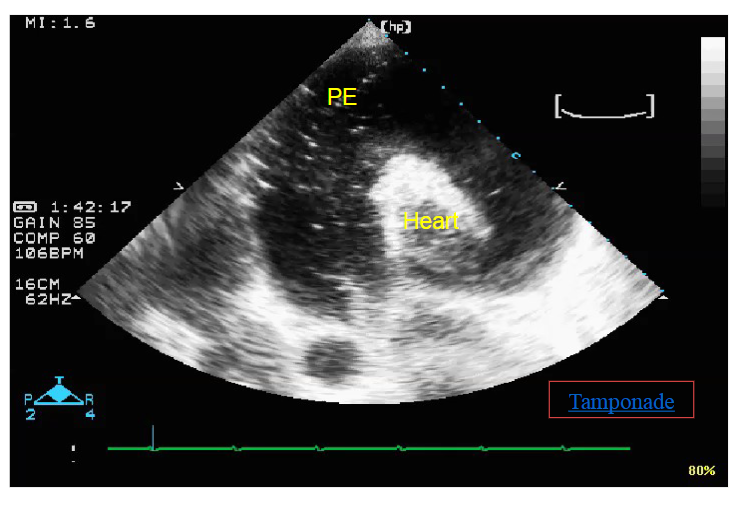

What does this image represent?

A

Air bubbles injected to confirm needle locations

Large pericardial effusion